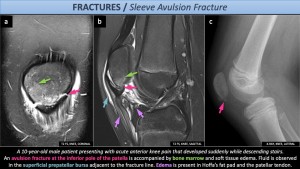

Sleeve avulsion fracture:Sleeve avulsion fractures occur in children aged 8–12 years and result from traumatic avulsion of the inferior pole of the patella due to forceful quadriceps contraction with the knee in flexion. This injury resembles Sinding-Larsen–Johansson syndrome but differs by its acute onset following trauma[4].